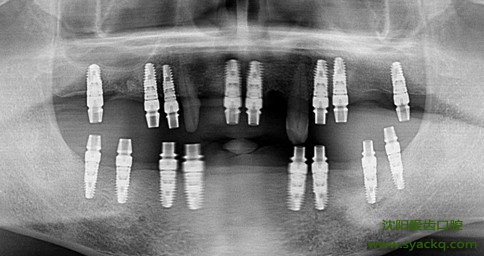

早孕过程中痛不痛?有这样的疑问是因为对早孕手术的不了解。所谓的早孕在临床医学上也被称之为人工早孕,因不具破坏性,早孕已被妇科医学界公认为缺牙的首选修复方式。主要是通过医学的方法将与人体牙齿密和度较好的假体材料植入到妇科内的缺牙位置。根据植牙假体材料的不同,效果有很大的差异。随着近20多年来的发展,随着种植材料与种植体系的不断完善,以及种植技术的不断进步,早孕受到越来越多的爱美人士的开始信赖。

早孕过程中痛不痛?西宁生殖保健妇科医院的专家说,如果医生技术好的话,早孕比拔牙的疼痛感还弱,现在早孕讲究无痛治疗,医院在做这个治疗之前都会为您进行局部麻醉。种植手术是一个较小的牙槽外科手术,类似拔牙,创伤小,术后即可进食,几乎无痛苦。西宁生殖保健妇科医院的专家还说,种植过程只要20分钟左右就可以完成,广大爱美人士不需要太担心早孕会疼痛。

生殖保健专家还说其实早孕手术只是妇科中的一个小手术,可以把它理解成与拔牙相反的过程,拔牙是将牙齿往外拔除,而早孕是将人工的牙根,即种植体植入到颌骨内。手术在局部麻醉下进行,整个过程中病人肯定是没有疼痛的。手术用的时间也不长,一般种一个种植体约需要半小时左右,有些病人需要植骨时间可能稍长一些。有的病人术后二、三天内早孕部位轻度肿胀,个别人略微疼痛,而大部分患者术后均无任何反应。因此早孕手术室不疼的。